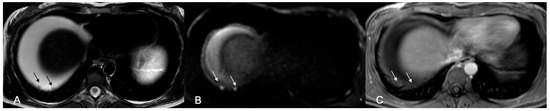

Figure 1